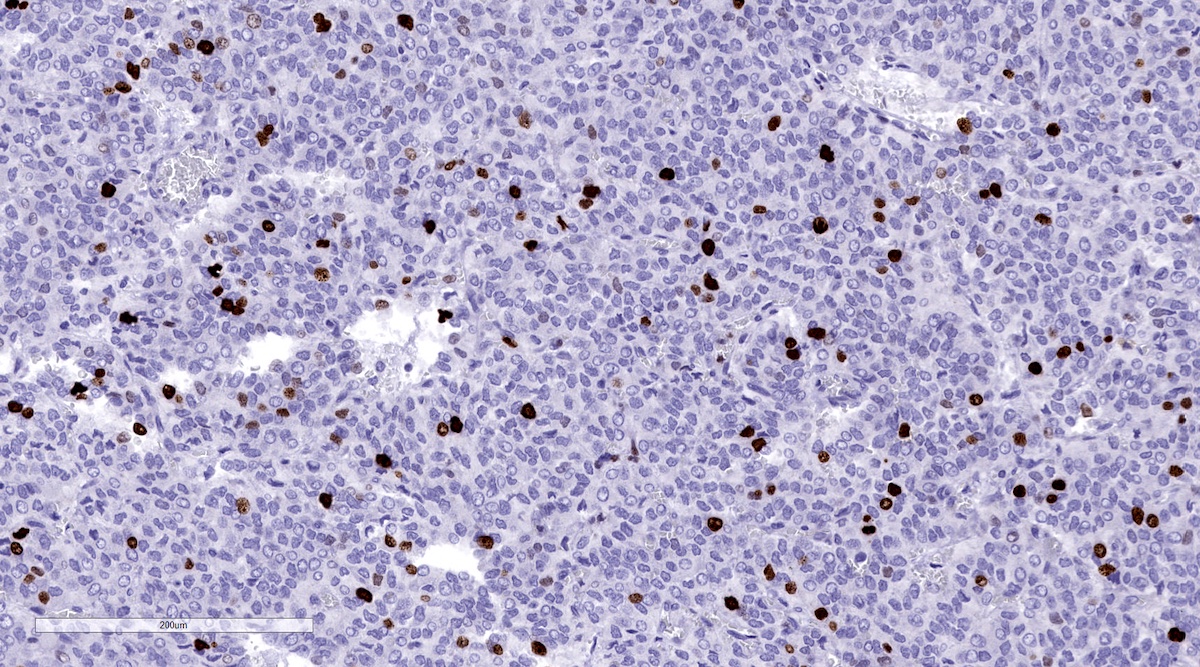

Microscopic (histologic) images

Contributed by Luvy Delfin, M.D. and Sylvia L. Asa, M.D., Ph.D.

Positive stains

- INSM1 (diffuse nuclear) (Am J Surg Pathol 2018;42:665)

- Chromogranin A (can be only focal or perinuclear dot-like golgi pattern)

- Synaptophysin (Histol Histopathol 1993;8:429)

- CD56 (Endocr Pathol 2002;13:149)

- S100 may be diffusely positive (J BUON 2018;23:1540)

- GATA3 (diffuse nuclear) (Hum Pathol 2020;103:72, Am J Surg Pathol 2014;38:13, J Clin Med 2018;7:280)

- Tyrosine hydroxylase (critical enzyme required for catecholamine synthesis; usually diffuse and strong in sympathetic paragangliomas, may be weak or focal in parasympathetic tumors) (Hum Pathol 2020;103:72)

- Dopamine beta hydroxylase and phenylethanolamine N methyltransferase (PNMT) (epinephrine producing tumors) (see Diagram below) (Neuroendocrinology 2015;101:289, J Clin Med 2018;7:280)

- Sustentacular cells: S100, GFAP and SOX10 (Hum Pathol 2020;103:72)

Contributed by Luvy Delfin, M.D. and Sylvia L. Asa, M.D., Ph.D.